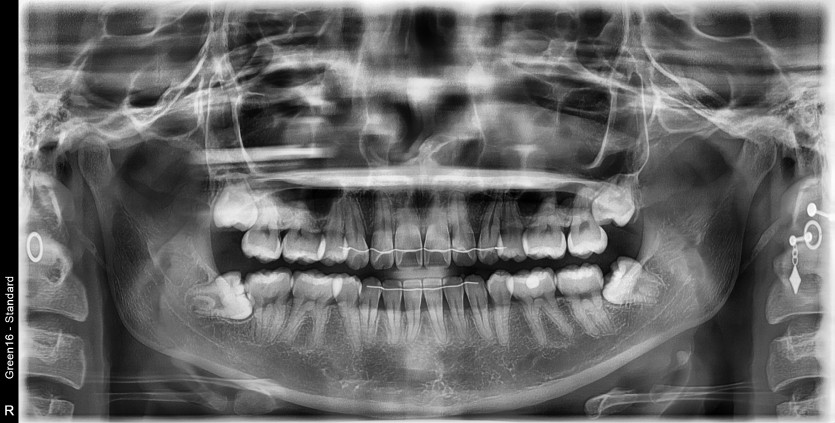

#38,48 사랑니 발치

구강 외과 전문의가 당일 발치했습니다.